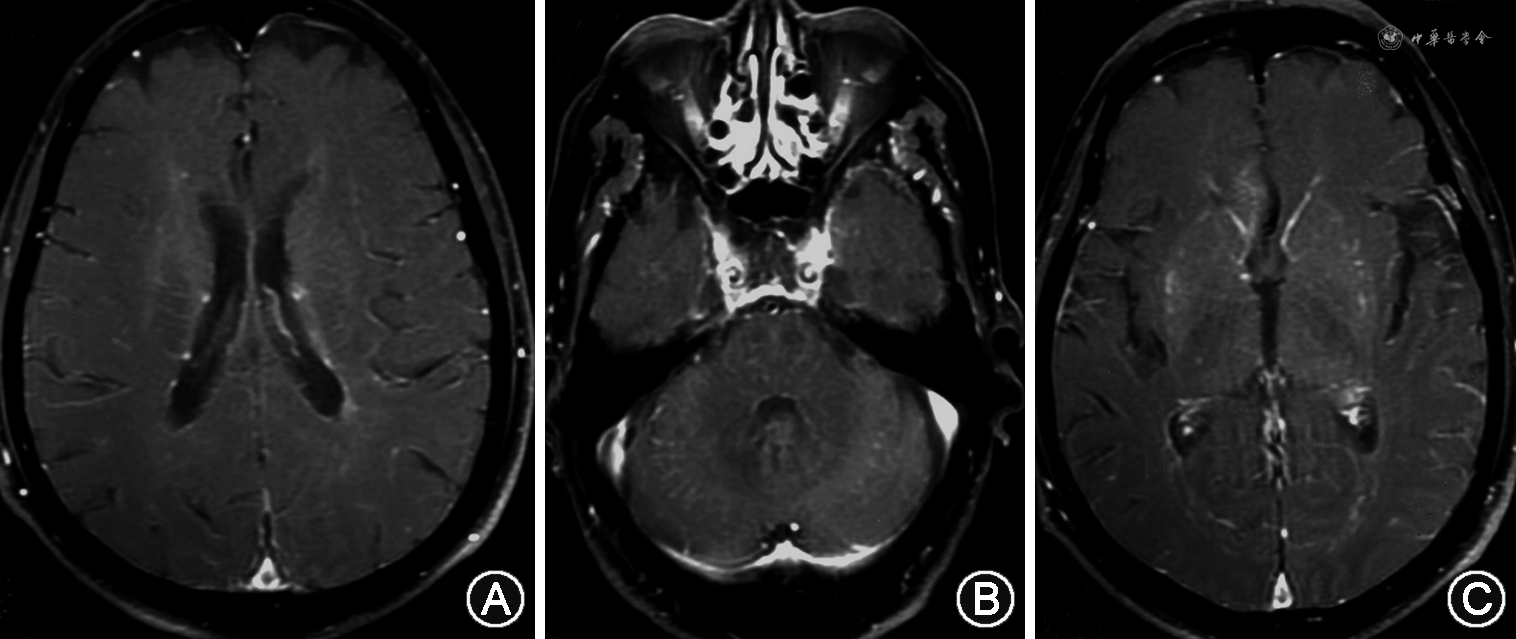

1.头颅MRI:大多数GFAP-A患者头颅MRI检查异常,可累及大脑皮质、基底节区、脑室周围白质、下丘脑、脑干、小脑、脑膜以及颅骨等部位。多数情况下是侧脑室旁散在的细线样的在轴位上垂直于侧脑室的长T1、T2信号,FLAIR上是更明显的高信号,无明显占位效应,脑室周围病变恶化可进展为广泛性脑白质病变。Kimura等[7]报道最常见的异常信号位于基底节,其次是丘脑,认为双侧丘脑后部高信号是其特征性的表现。患者DWI通常是正常的。约半数患者头增强MRI异常,典型表现为从侧脑室向外延伸的血管周围线样放射状强化,常见淡淡的线状强化(图1A),容易被忽略,小脑也可有这种强化[1,4,16](图1B)。Mirian等[25]发现1例患者表现出从延髓和脑桥腹侧发出的线状放射样强化。其他还可有软脑膜强化(图1C)、点状强化、蛇形强化和室管膜强化[4]。